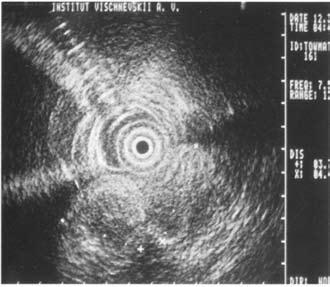

Достаточно достоверные данные о местном распространении опухоли, инвазии сосудов, регионарных метастазах могут быть получены при использовании эндоультрасонографии (ЭУСГ) – нового метода диагностики, эффективность которого широко обсуждается в литературе. При этом исследовании датчик можно подвести непосредственно к опухоли (лапароскопически, через желудок и ДПК, интрадуктально через БДС, интрапортально), что позволяет выявить образования менее 1 см, а при интрадуктальном УЗИ – опухоли до 2 мм, увеличенные лимфатические узлы, инвазию крупных сосудов, выполнить игловую биопсию этих образований. Недостатком ЭУСГ является большая зависимость результатов исследований от опыта врача, выполняющего исследование, что существенно ограничивает его применение и мешает широкому распространению метода (рис. 102). В последнее время значительную роль в решении вопросов диагностики и определении стадии РПЖ играет позитронная эмиссионная томография (ПЭТ). ПЭТ позволяет осуществлять количественную оценку концентрации радионуклидов в опухоли и пораженных ею лимфатических узлах на разных стадиях заболевания.

Рис. 102. Эндоскопическое УЗИ. 1. Опухоль головки ПЖ. 2. Расширенный терминальный отдел общего желчного протока